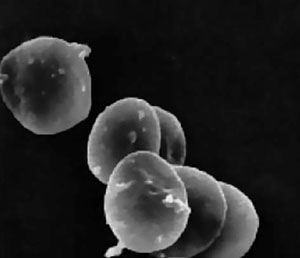

Тромбоциты (от греч. θρομβοζ — ‘сгусток’ и κυτοζ — ‘клетка’) — специализированные безъядерные клетки крови, имеющие форму диска диаметром около 3 мкм и толщиной около 0,5 мкм (рис. 1). Образуются они при фрагментации больших клеток костного мозга — мегакариоцитов и циркулируют в кровотоке в концентрации 200–400 тыс. клеток в 1 мкл крови. Живут тромбоциты в кровотоке в среднем 5–9 дней, а затем разрушаются в селезенке и печени.

Рис. 1. Микрофотография неактивированных тромбоцитов [1]